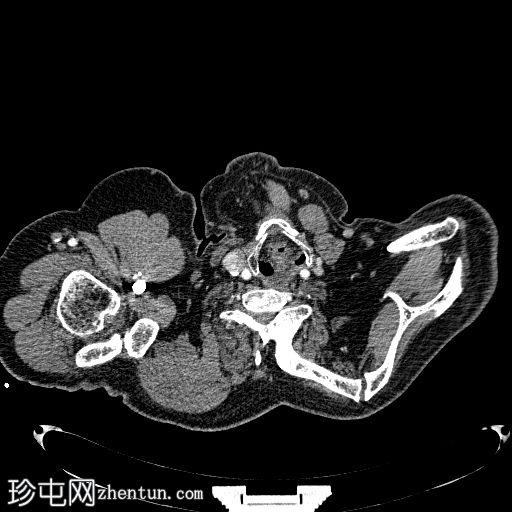

轴位

平扫

颈椎区域可见生理性颈椎前凸变直,伴有下颈椎椎间盘明显变窄,以及相应椎体部分融合(椎体融合)。

同时,左侧肩胛骨抬高,在肩胛骨内侧缘与颈椎之间可见一长约10厘米的肩胛椎骨。

这些影像学表现符合伴有肩胛椎骨的Sprengel畸形。